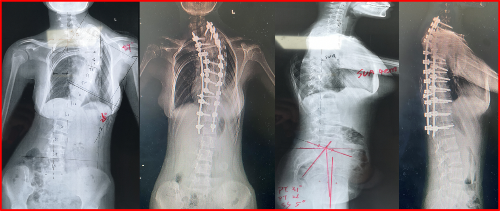

图二 术前及术后全脊柱正侧位对比,侧凸畸形得到明显矫正,术后双肩对称